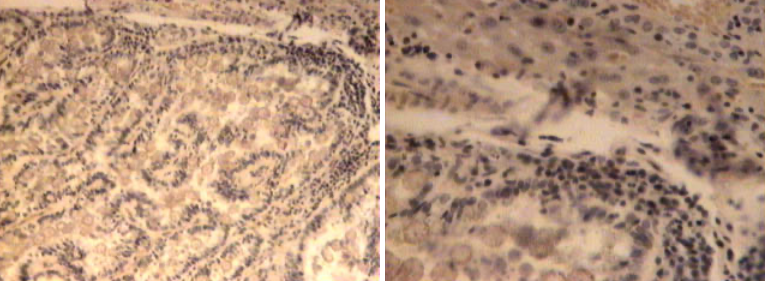

Alaäge glomerulonefriit

Krooniline glomerulonefriit